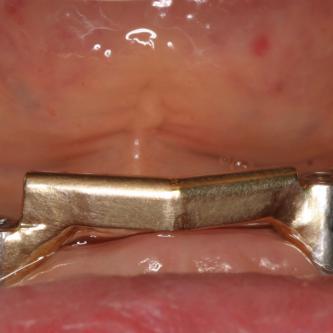

Exemple 9: Un cas complexe, 3 implants on été mis au niveau de la mandibule.

Exemple 9: Une barre est vissée sur ces 3 implants.

Exemple 9: Puis un appareil amovible est fixé sur cette barre.